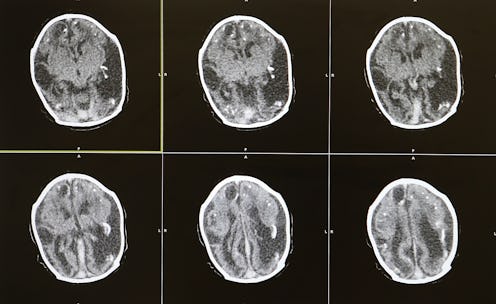

In a study published in the journal Nature, a research team led by Susumu Tonegawa explored how emotions get attached to memories, as well as how those emotions can be manipulated to turn an experience remembered as “bad” to one recalled as “good.” According to TIME, his involved finding where in the brain positive and negative memories are created — something that’s never been done before. Ever. By using a technique they called “optogenetics,” the researchers first tracked emotional memories as they were made in the brains of mice: Administering a specific protein (channelrhodopsin—gibberish to me, but maybe it sounds like something to the scientifically inclined out there) into nerve cells of mice that activated both during and immediately after positive and negative experiences—male mice spending an hour with female mice for the positive ones, and getting a mild foot shock for the negative ones. The protein reacts to a specific wavelength of laser light; when the researchers administered that light to the nerve cells, the mice relived the emotion associated with that experience, even without the experience itself occurring again.

Then they got fancy. The researchers put the mice who had previously gotten shocked in with a female— taking them from the negative experience into the positive one. Then they administered the laser light again, which caused the mice to relive the fear they associated with the shock again. The mice relaxed after about 12 minutes — and the researchers found when they did so that new circuits had grown between the brain’s emotional regions and its memory center. The same thing happened when they put the mice who had previously experienced the positive condition into the negative one. This demonstrates not that one emotional memory replaces the other; rather, it shows that the positive and negative circuits end up having a contest of sorts—and whichever one wins out becomes the emotion linked to a specific memory. Essentially, they hacked the mice’s brains and rewired how they felt about each experience.